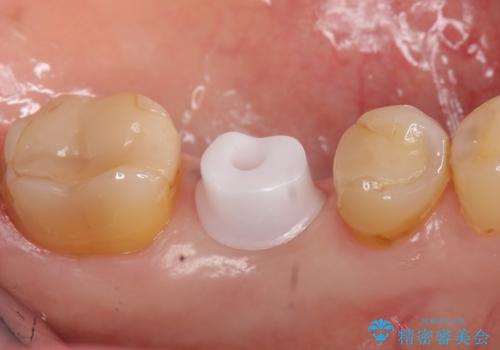

カスタムアバットメントは患者様それぞれの歯茎に合わせて製作されたオーダーメイドのアバットメントです。

既製のアバットメントに比べ適合がよく、高い清掃性を誇ります。